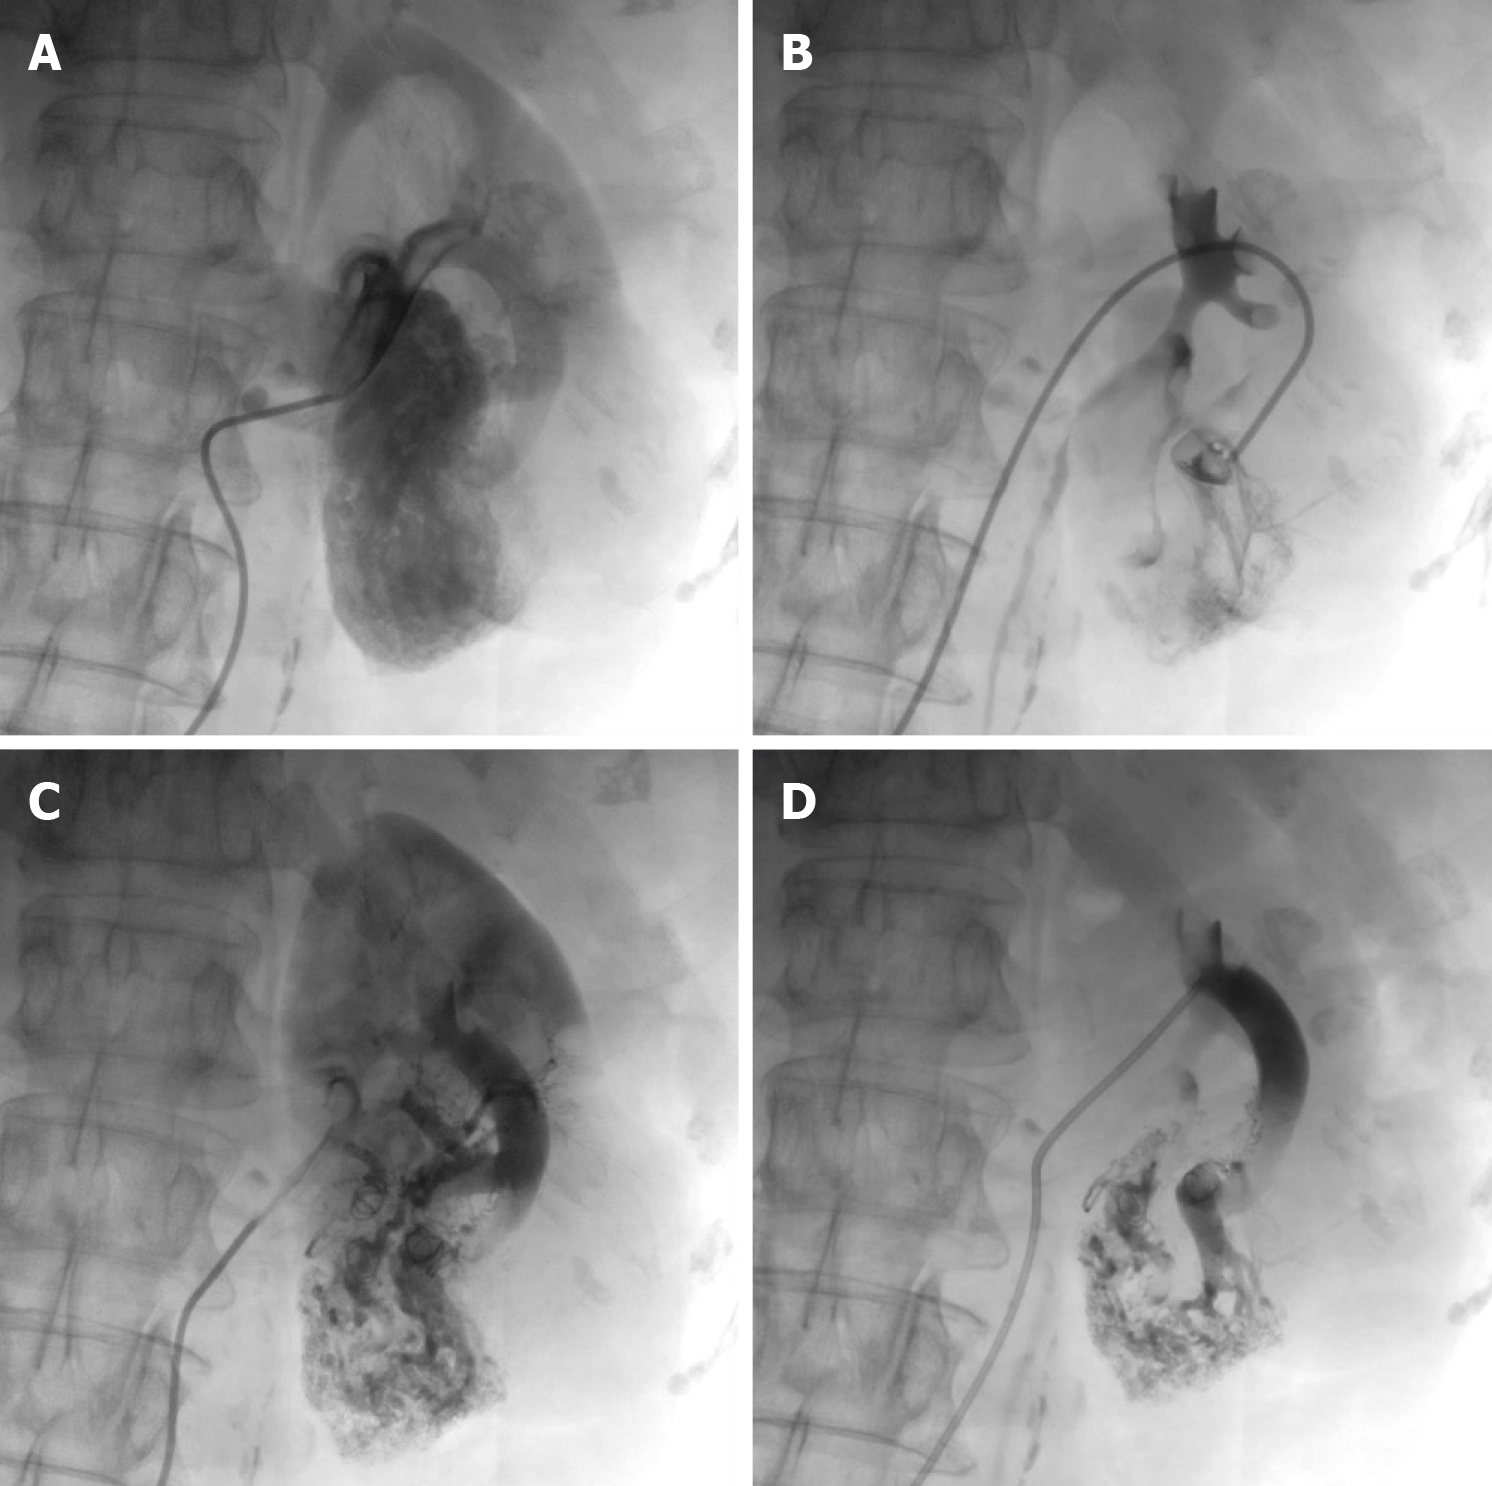

In addition to being the gold standard for diagnosing RAVF, DSA also has a therapeutic role. Because DSA is an invasive procedure, if the family agrees to the treatment, DSA can play a dual advantage in the diagnosis and treatment of RAVF. On July 3, 2023, after the patient and his family signed an informed consent form, the patient underwent DSA of the left renal artery under local anesthesia. RAVF formation was observed in four branches of the left renal artery with contrast medium extravasation, and significant lamellar vascular malformations were observed in the lower pole of the left kidney (Figure 6A and B).

The patient underwent left renal artery embolization immediately after renal arteriography. The diseased branches of the left renal artery were embolized with five spring coils. Postoperative imaging confirmed complete embolization of the blood-supplying vessels of the lesion (Figure 6C and D).